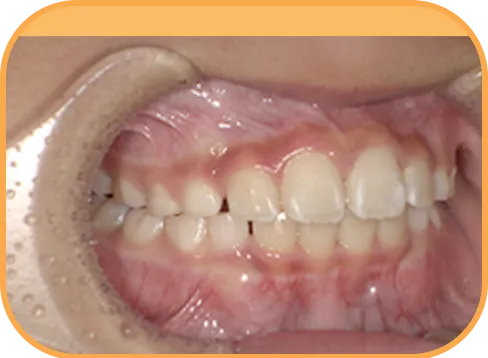

• After

• 正 面

治療後正面からの歯の様子

• 上 顎

治療後上顎からの歯の様子

• 下 顎

治療後下顎からの歯の様子

• 右 側

治療後右側からの歯の様子

• 左 側

治療後左側からの歯の様子

主 訴

前歯がでている、噛み合わせが深い

治療内容

インビザライン・ファースト

治療期間

10か月

治療費(税別)

450,000円+診断料30,000円

リスク・副作用

• 親知らずの影響や加齢などによって、凸凹が生じる可能性があります。

• 治療の初期段階では痛みや不快感が生じやすくなりますが、1週間前後で慣れます。

• 顎の成長発育によって、噛み合わせや歯並びが変化する可能性があります。

• 状況により当初予定した治療計画を変更する可能性があります。